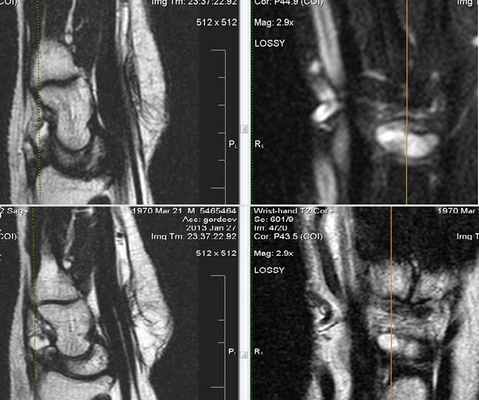

После операции лучезапястный сустав фиксировался иммобилизационной повязкой сроком на 4 недели. По окончанию срока иммобилизации пациентке была рекомендована постепенная разработка лучезапястного сустава, исключающая осевые нагрузки. Через 6 недель с момента операции пациентке было выполнено МРТ исследование для осуществления контроля положения восстановленной связки (рис. 5).

Рис. 5. МРТ исследование правого лучезапястного сустава. На МРТ сканах во фронтальной плоскости: 1) отмечается восстановление пространства между ладьевидной и полулунной костями, отчетливо видна связка; верифицируется биодеградируемый пин и якорный фиксатор в ладьевидной кости; 2) отмечается синовит лучезапястного сустава и отсутствие отека костной ткани ладьевидной кости